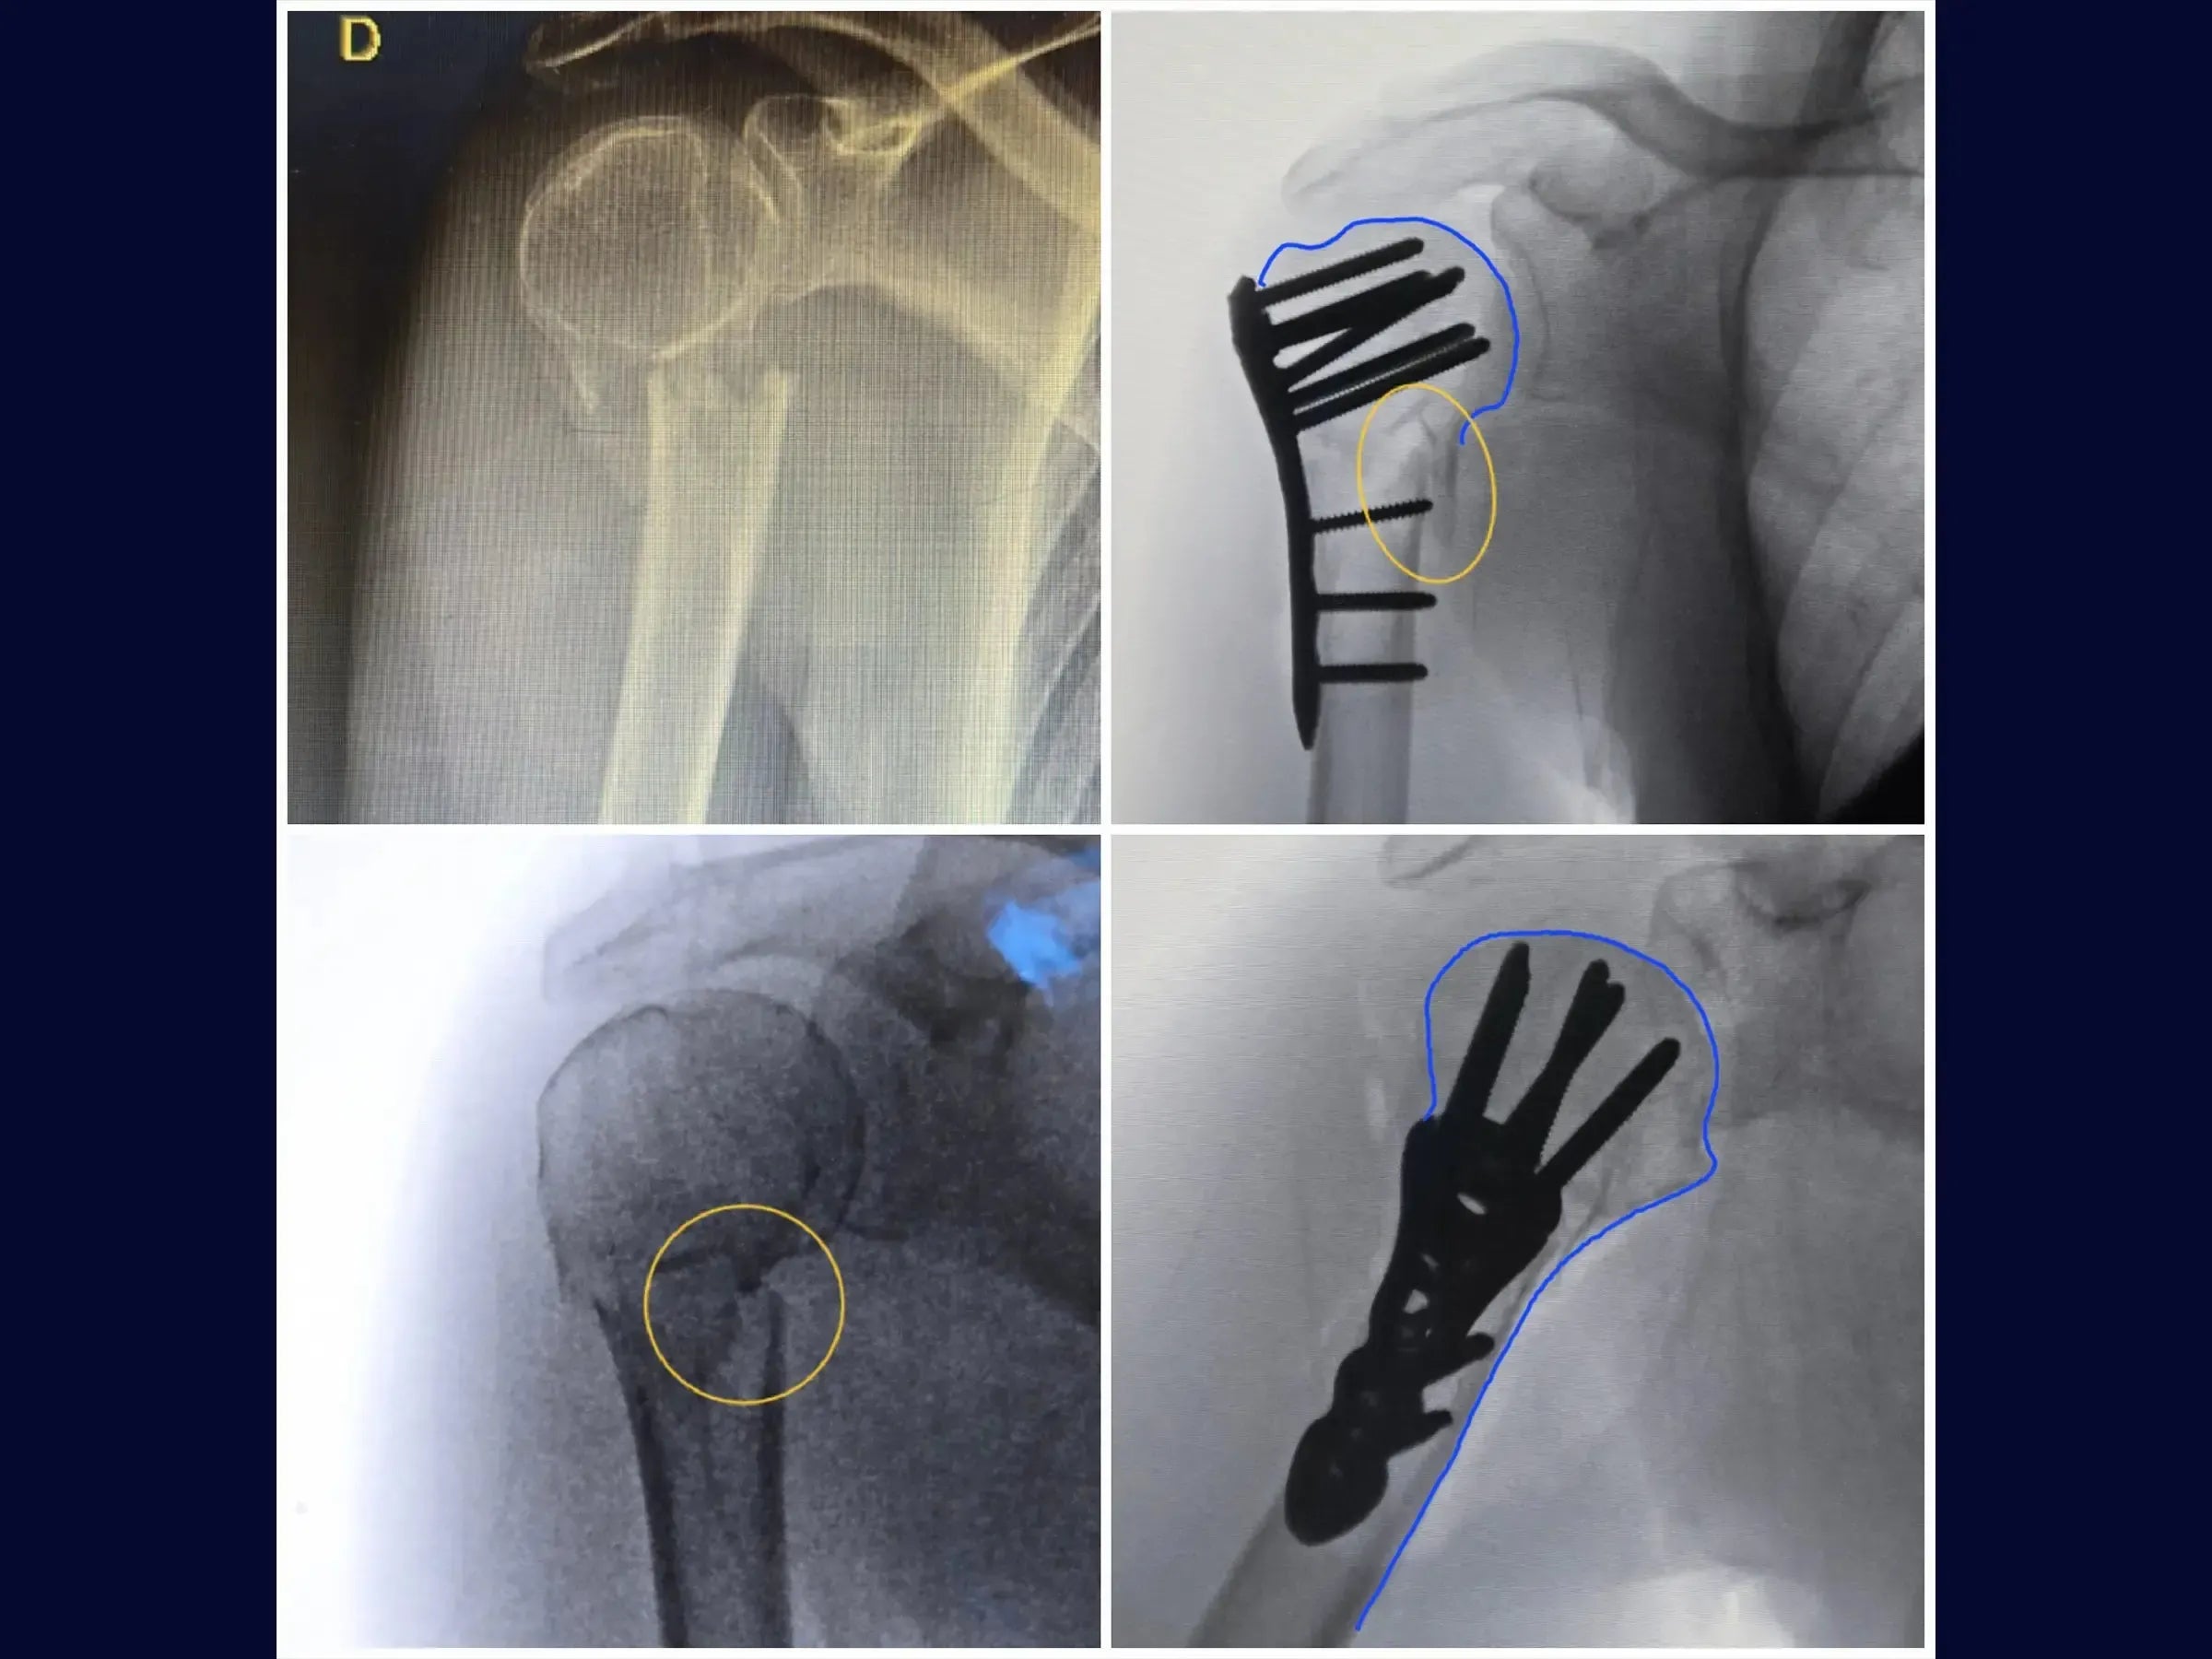

- Anatomical reduction of proximal humerus fractures and provisional fixation.

- Manoeuvres for valgization of the humeral head.

- Brocage technique and measurement of screws for definitive subchondral fixation.

- Correction of Varus: Specific maneuvers (abduction, traction with high-resistance wire, thumb pressure, and inverted condylar grip) for valgization of the humeral head.

- Secure Subchondral Fixation: Drilling methodology with sensitivity for precise positioning of screws in the subchondral bone, without perforating the cartilage, with initial insertion of the screws from the calcaneus.

- Post-Operative Stability: Demonstration of the rotator cuff repair to the plate for additional stabilization, especially in osteoporotic bones, and management of the long head of the biceps.